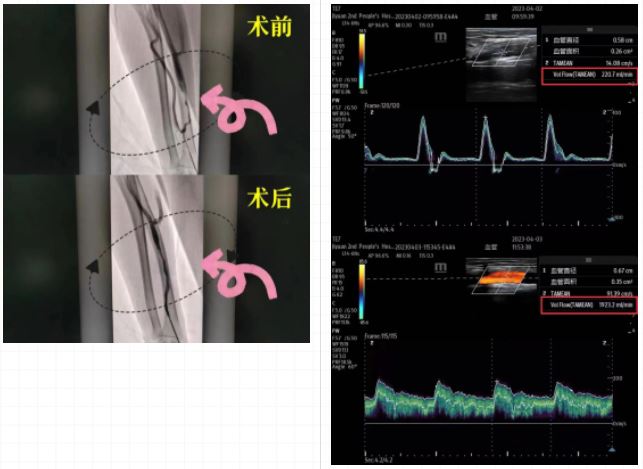

1周前赵先生开始发愁了,因为他的内瘘处震颤减弱,血液透析血流量降低,听到透析时透析机滴滴的报警声,赵先生双眉紧锁,愁云满布。副主任张佳佳随即对其进行超声检查,发现患者动静脉内瘘吻合口上方出现狭窄,血管通路使用影响,经与患者及家属沟通后,决定行DSA引导下内瘘球囊扩张术,使之能继续满足透析要求。DSA下,患者头静脉多处狭窄,内膜粗糙,血流通过受阻,由蒋主任带领的通路团队在DSA下给予动静脉内瘘球囊扩张,血流通过顺畅。术后蒋主任再次对其动静脉内瘘进行评估,肱动脉血流量由术前的220ml/min变为1923ml/min。

当赵先生再次摸到强劲的内瘘震颤,他知道生命通路已经恢复正常,露出了喜悦的笑容。术后患者第二天行血液透析治疗,内瘘流量达到透析要求,透析机平稳运行,手术取得圆满成功。